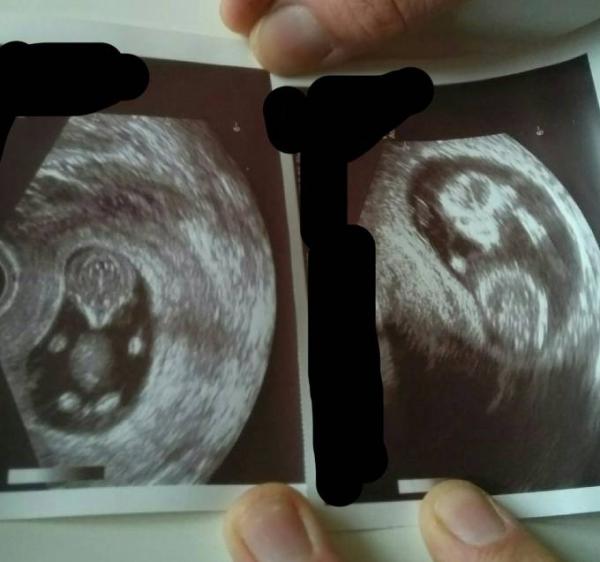

Das Bild ist rechts von unseren Sohn und links vom Baby. Beide am 3.1